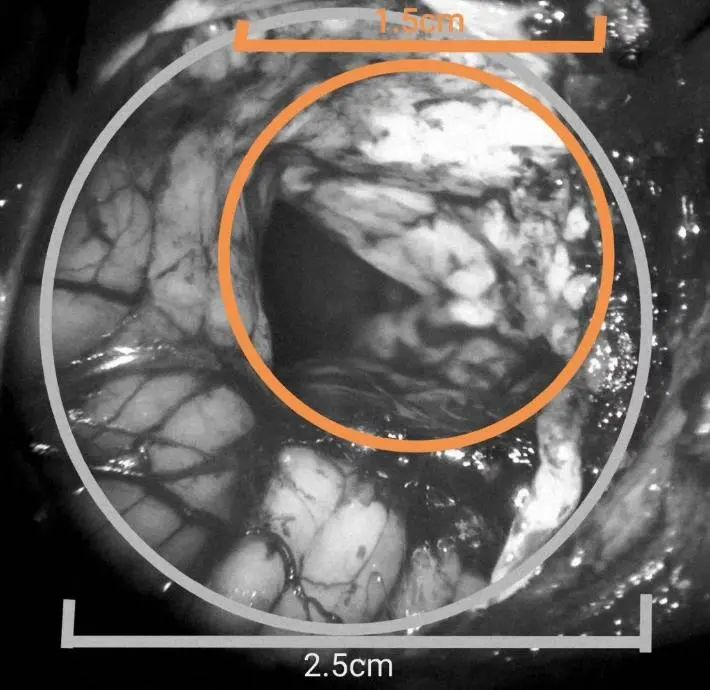

手术行左侧旁正中入路,应用锁孔通道技术,骨孔直径2.5cm,皮层通道1.5cm,先用内镜清除血肿,ICP下降,显微镜下清除IV脑室内积血,责任血管止血可靠,术毕。术后病人意识水平明显改善,刺激睁眼,双侧肢体自主活动。复查头CT显示小脑血肿清除满意。突发头痛,意识不清1小时。既往高血压病史多年,未系统治疗。自主呼吸深大,瞳孔正常大小。CT显示小脑蚓深部大量脑内血肿,IV脑室受压移位,III脑室及侧脑室内积血,左侧丘脑少量出血。

术后病人意识水平明显改善,刺激睁眼,双侧肢体自主活动。复查头CT显示小脑血肿清除满意,左侧丘脑内血肿未见增加,治疗中…手术行枕下正中入路,应用锁孔通道技术,吸除脑内血肿,进一步清理IV脑室内积血,责任血管止血可靠,术毕。骨孔直径2.5cm(图3白色圈为骨孔范围),皮层通道直径1.5cm(图中黄色圈为皮层通道直径)。术后病人生命指标稳定,呼吸节律正常,瞳孔正常,意识水平较术前明显好转。复查头CT可见血肿清除满意。